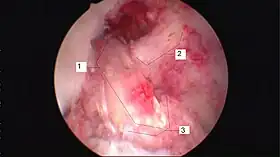

Arthroscopic anterior cruciate ligament (ACL) reconstruction (right knee). The tendon of the semitendinosus muscle was prelevated, folded and used as an autograft (1). It appears through the remnant of the injured original ACL (3). The autograft then courses upwardly and backwardly in front of the posterior cruciate ligament (2). | |